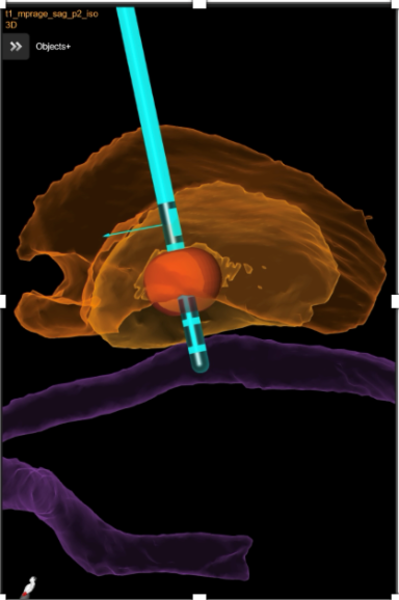

Bei bestimmten Bewegungsstörungen, die nicht oder nicht mehr ausreichend auf eine medikamentöse Therapie ansprechen, ist es möglich, die hierfür verantwortlichen Hirnareale durch die sog. Tiefe Hirnstimulation zu beeinflussen. Hierbei werden feine Elektroden in das Gehirn eingesetzt, um fehlerhafte Nervenstrukturen mit elektrischen Impulsen zu aktivieren oder zu hemmen. Beim Morbus Parkinson, dem essentiellen Tremor oder der Dystonie sind beispielsweise spezifische Hirnareale überaktiv, die dann gezielt durch die Tiefe Hirnstimulation gehemmt und die Symptome wie Zittern oder Muskelsteifigkeit dadurch unterdrückt werden können. Die Hirnregionen selbst bleiben dabei intakt, sodass die Stimulation jederzeit rückgängig gemacht werden kann. Die elektrische Stimulation wird durch einen Impulsgeber gesteuert, der ähnlich wie ein Herzschrittmacher unter die Haut an der Brust der Patient:innen implantiert wird. Die Einstellungen des Impulsgebers lassen sich von außen jederzeit verstellen, sodass die Stimulation an veränderte Bedürfnisse der Patient:innen stets angepasst werden kann.